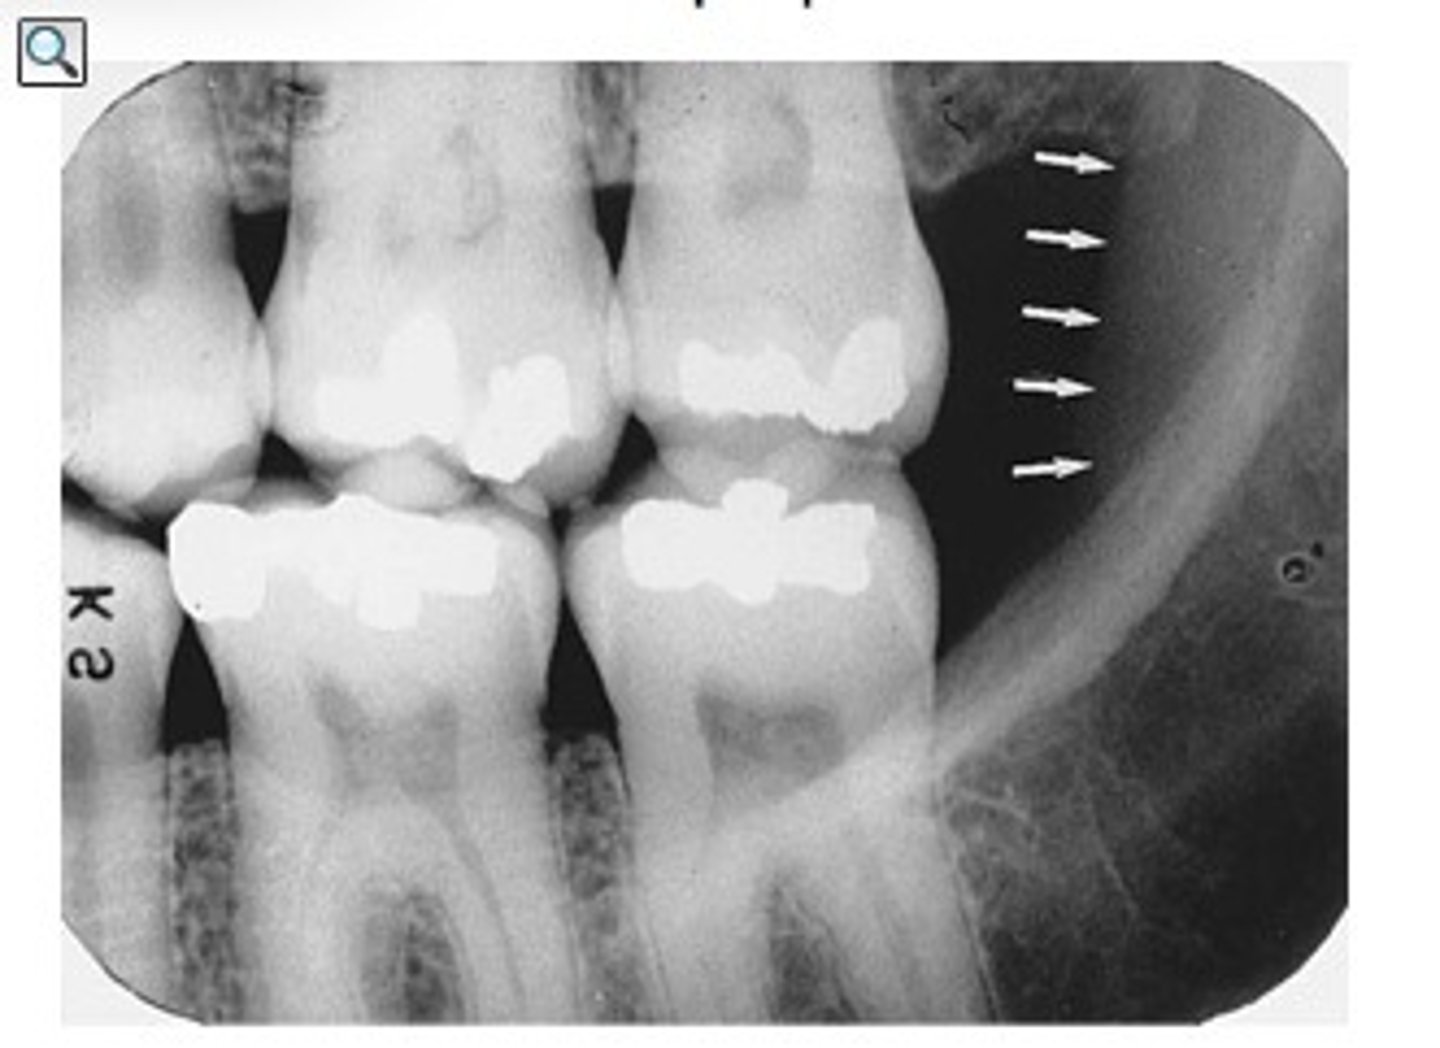

what is this?

what is this radiolucent area in the image?